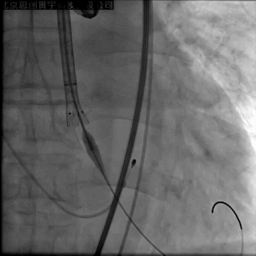

22mm球囊后扩

复查彩超,瓣膜贴壁良好,无瓣周漏,残余压差<10mmHg

术后即刻LVEF 35.4%,较术前显著改善